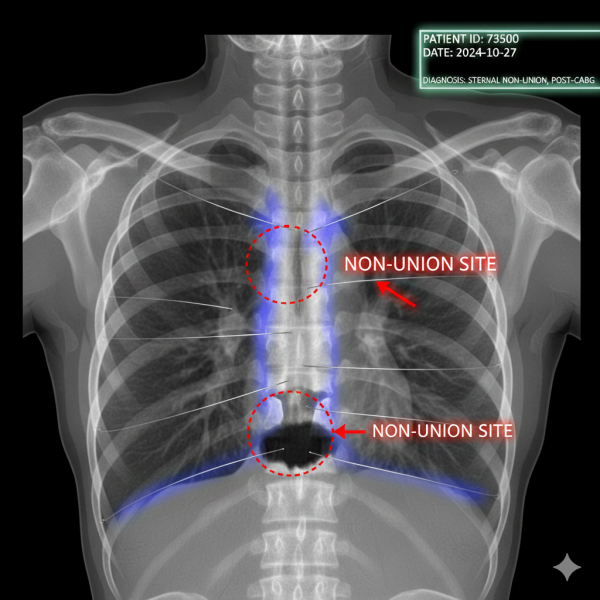

Failure of the Chest Bone Fracture to Achieve Union Presents a Major Risk Factor for Long-Term Disability

Sternum Breakdown After Heart Surgery

Wound and Bone Healing Problems, Causes of Non-Union, and Complications

Breastbone Fracture after Heart Surgery

What causes the breastbone to split apart after heart surgery?